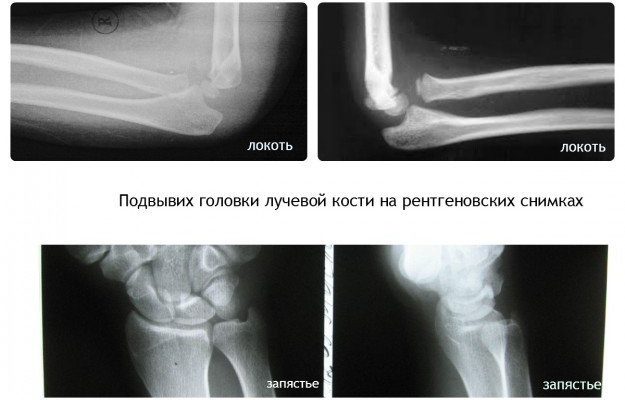

Иногда хирург-травматолог может порекомендовать сделать рентгеновский снимок ребенка. Дополнительная диагностика обычно необходима при подозрении на перелом или прине удалось добиться правильной репозиции головки лучевой кости.

Если у врача есть сомнения в диагнозе, просто необходима дополнительная диагностика, поэтому родителям не стоит отказываться от проведения рентгена ребенка. При подтверждении радиального вывиха изменений сустава на фото не видно.